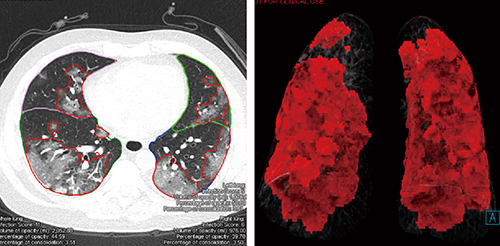

1つ目の機能は陰影の検出と定量化である。ディープラーニングによってトレーニングされたアルゴリズムにより,COVID-19患者に一般的に認められる異常所見である「すりガラス状陰影(GGO)」と「浸潤影(以下,consolidation)」が検出・セグメンテーションされ(図1),肺全体,片肺,および5つの肺葉単位で,下記の指標で定量化される。

図1 CTPA Prototype解析結果画像